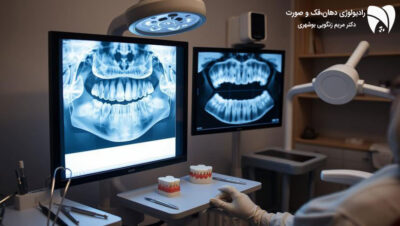

رادیوگرافی پانورامیک برای بررسی کلی وضعیت فک و دندان‌ها

رادیوگرافی پانورامیک یکی از روش‌های معمول و ضروری برای بررسی کلی وضعیت فک و دندان‌ها در ارتودنسی است. این رادیوگرافی تصویری گسترده از تمامی دندان‌ها، فک و ساختار استخوانی مرتبط ارائه می‌دهد و به دندانپزشک کمک می‌کند تا مشکلات نهفته مانند دندان‌های نهفته، کیست‌ها، و تومورها را شناسایی کند. این نوع رادیوگرافی همچنین در بررسی مراحل رشد دندان‌ها و تعیین زمان مناسب برای شروع درمان ارتودنسی مفید است.